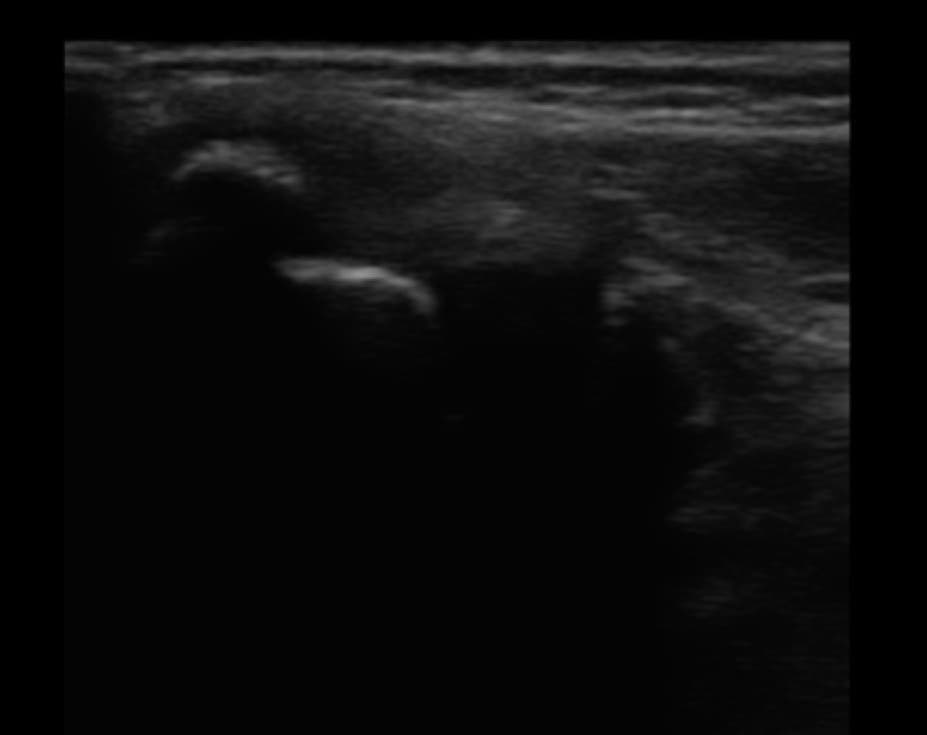

① 超音波エコーによる画像検査

当院では、超音波エコー診断装置を取り入れているので骨、靭帯、筋肉、軟骨の状態の把握出来ます。どの部分の痛みなのか、どのくらいの治療期間なのか、改善状況もしっかり確認出来るので治療計画が明確にたてられます。